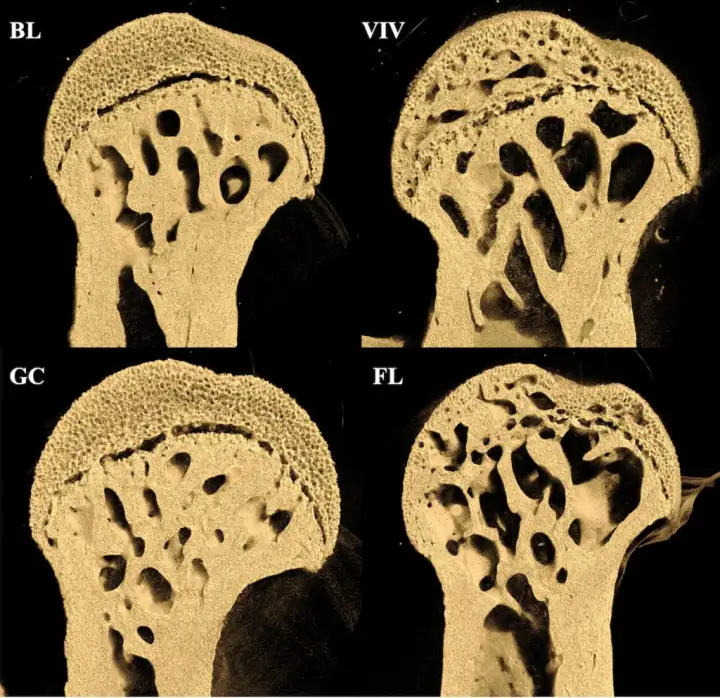

Сравнение головок бедренных костей у разных мышей. GC — кости здоровых мышей, в то время как FL показывает состояние костей мышей с МКС. Сравнение головок бедренных костей у разных мышей. GC — кости здоровых мышей, в то время как FL показывает состояние костей зверьков с МКС.© Rukmani Cahill et al., PLOS One

Оказалось, что потеря костной массы была неравномерной, однако она специфична именно для тех участков, которые нагружаются весом. Например, больше всего пострадали бедренные кости мышей, а не позвоночники. Скорее всего это связано с микрогравитацией, поскольку нет доказательств того, что данное состояние вызвано радиацией.